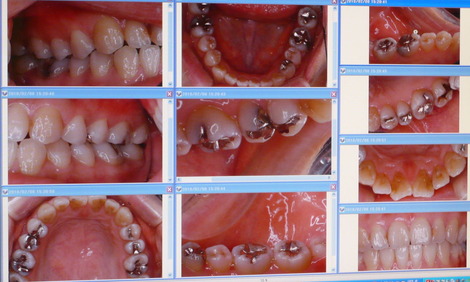

以前 このブログでも書きましたが、私は患者さん1人1人の口腔内写真

を撮影しています。

こんな感じです(*゚∀゚)っ

( * 画像のアップは患者さまの了解を得ております )

口腔内写真は基本、13枚撮影しており カメラNIKON D60

を使用しています。

治療計画を立てる時はもちろんのこと、治療が終わっていくにつれ、最初の状態と比較していくと、格段にお口の中がよくなっていくのが目につきます。

患者さんと一緒に治っていくのを確認して、さらに感謝される瞬間は、撮影してよかったな、歯科医師になって良かったなと思う瞬間でもあります(*^_^*)